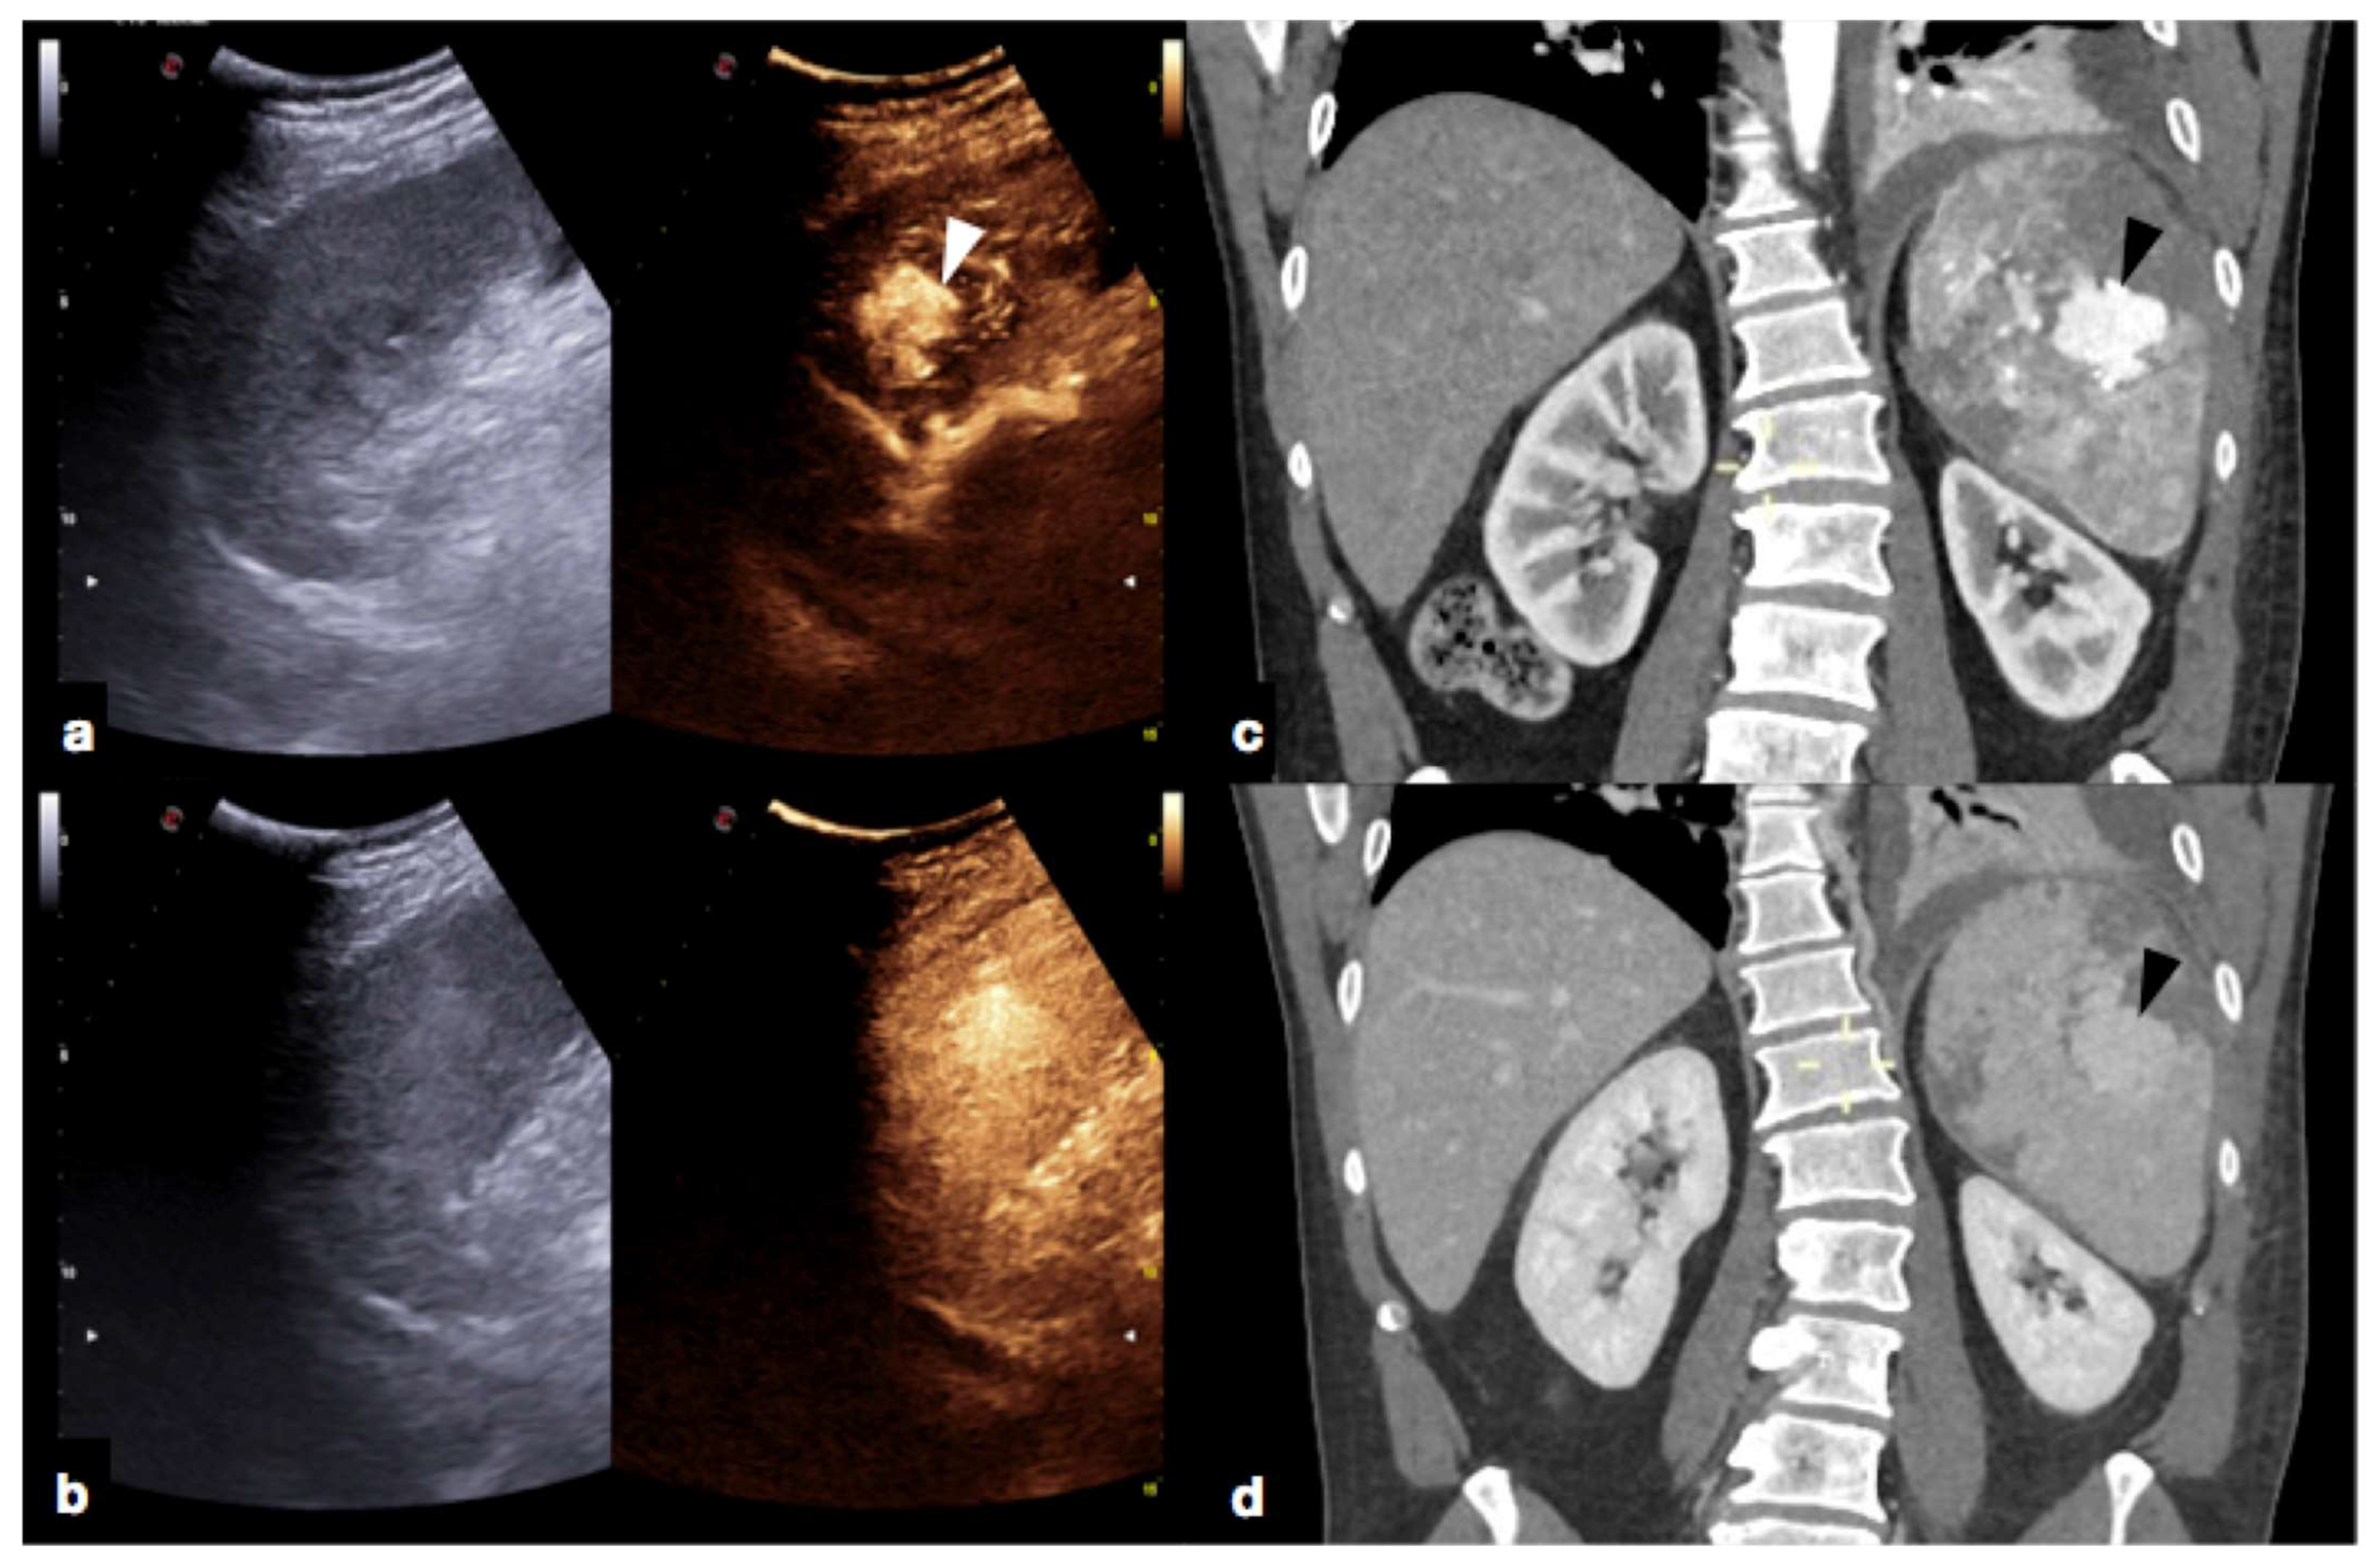

- Parenchymal injuries:

2.3.2. Vascular Injuries

- Contained vascular injuries: